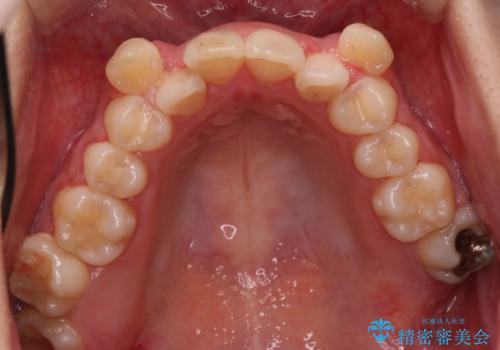

【抜歯矯正】犬歯抜歯による矯正。八重歯を治したい

- 八重歯を主訴に来院された患者様です。

インビザラインによる矯正を希望され、今回は移動距離が少なくなるように犬歯を抜歯する治療計画としました。

抜歯矯正において、通常では4番(第一小臼歯)が抜歯の対象となることが多いのですが、今回は3番(犬歯)の歯肉退縮や装置の特性を考慮した治療計画となります。